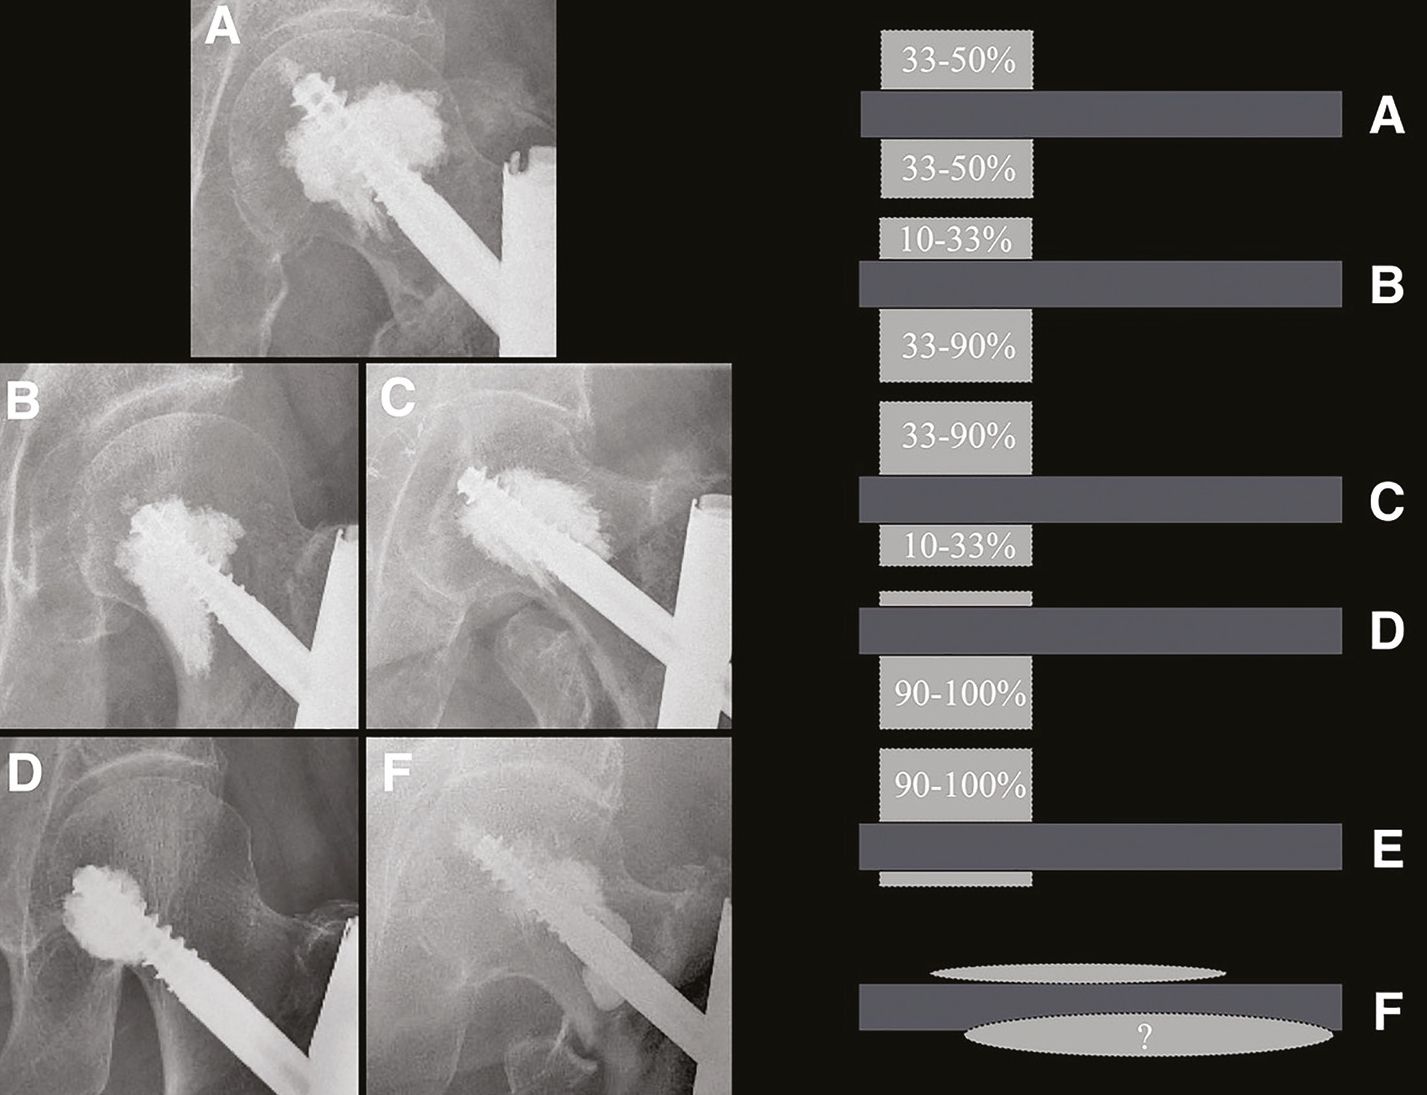

We found that the homogeneity of the cementing on the AP hip radiograph varied, and that the distribution of cement above and below the screw could be classified into 6 different types (Figure 6):

- type A: symmetrical distribution of cement (33-50%) above and below the screw.

- types B and C: moderate asymmetric cement distribution (10-33% on one side and 33-90% on the other), with the majority of cement below (type B) or above (type C) the screw.

- types D and E: major asymmetric distribution of cement (0-10% on one side and 90-100% on the other), with a majority of cement below (type D) or above (type E) the screw.

- type F: random distribution of cement that does not meet the criteria of types A-E.

Some surgeons prefer to position the cervicocephalic screw of the nail in the lower third of the femoral head to position itself under the dense centre of the femoral head. This leaves the screw head in medium quality bone, but with a better quality bone "ceiling" on which to rest under load. If an augmentation is undertaken with such a screw placement, the cement will diffuse into the lower part of the femoral head (less dense), but will not diffuse, or not well, into the middle third of the femoral head (more dense). This will result in a type D augmentation.

On the other hand, if the cervicocephalic screw is positioned in the dense centre of the femoral head (which some surgeons do not prefer since the "ceiling" is then of average quality), and an augmentation is performed, the cement will easily diffuse into the less dense areas, i.e. the upper and lower thirds, giving a more homogeneous, i.e. symmetrical (type A), or slightly asymmetrical (types B and C), cementation.